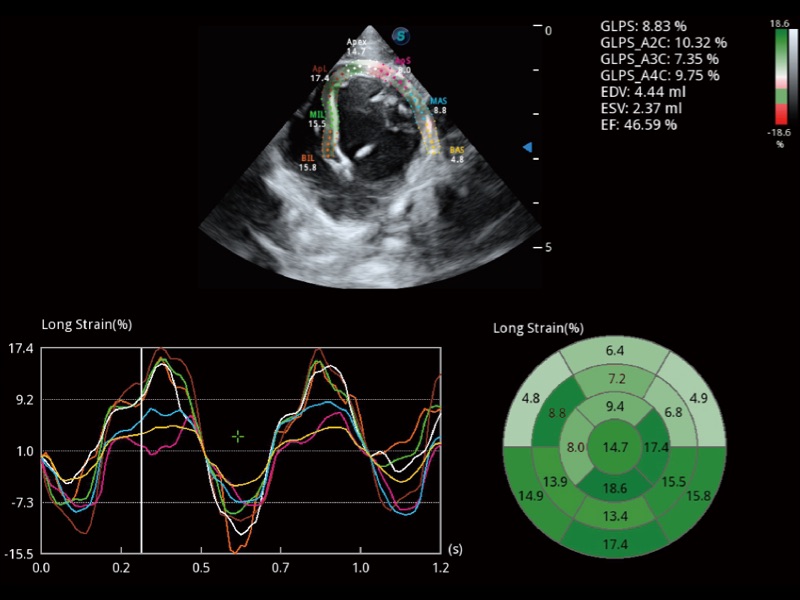

• Auto EF 心内膜自动描迹

能够基于左心室壁追踪和辛普森法,自动计算射血分数,支持多个可移动点描迹,与手动测量相比,极大节省了动物医生的时间和精力。

(犬)四腔心MQA